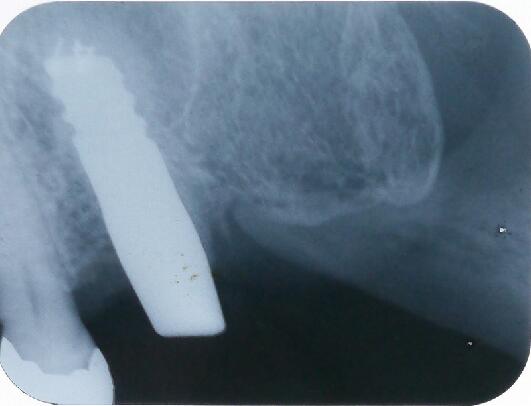

オペ当日のエックス線写真です